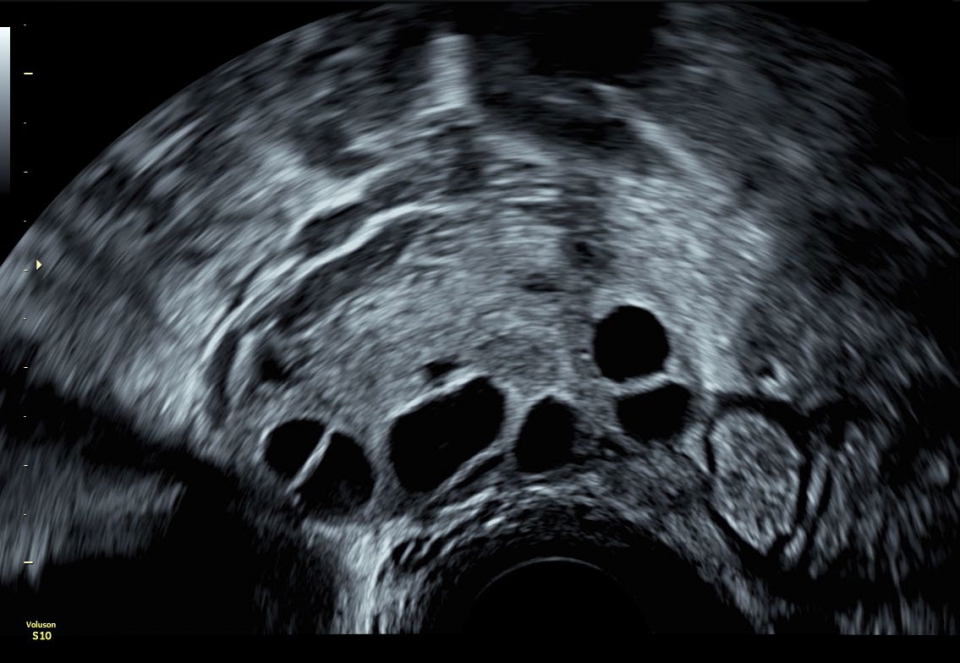

• SonoAVC (Автоматический расчет объема): Эта функция позволяет визуализировать и рассчитывать размеры и объем гипоэхогенных образований, таких как фолликулы яичника или структуры головного мозга плода. Она помогает в оценке этих образований и отслеживании их изменений в течение времени.